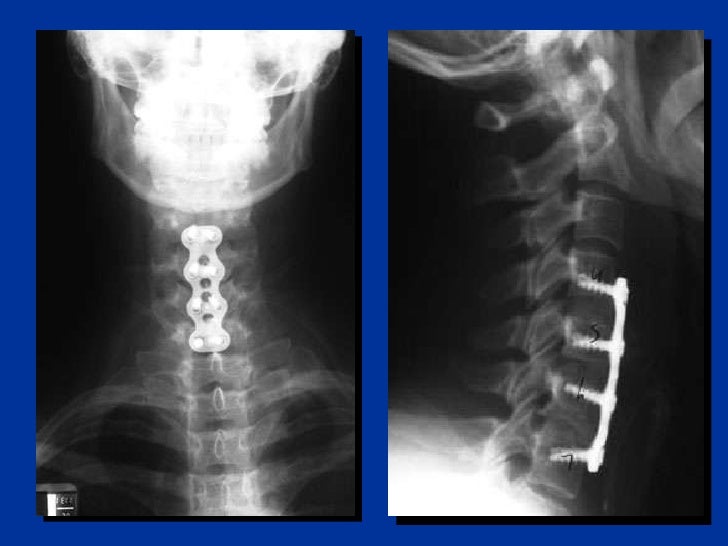

Neurosurgeons or orthopaedic surgeons manage any detected injury. Today, most large centers have spine surgery specialists, that have trained in this field after their orthopedic or neurosurgical residency.

After imaging